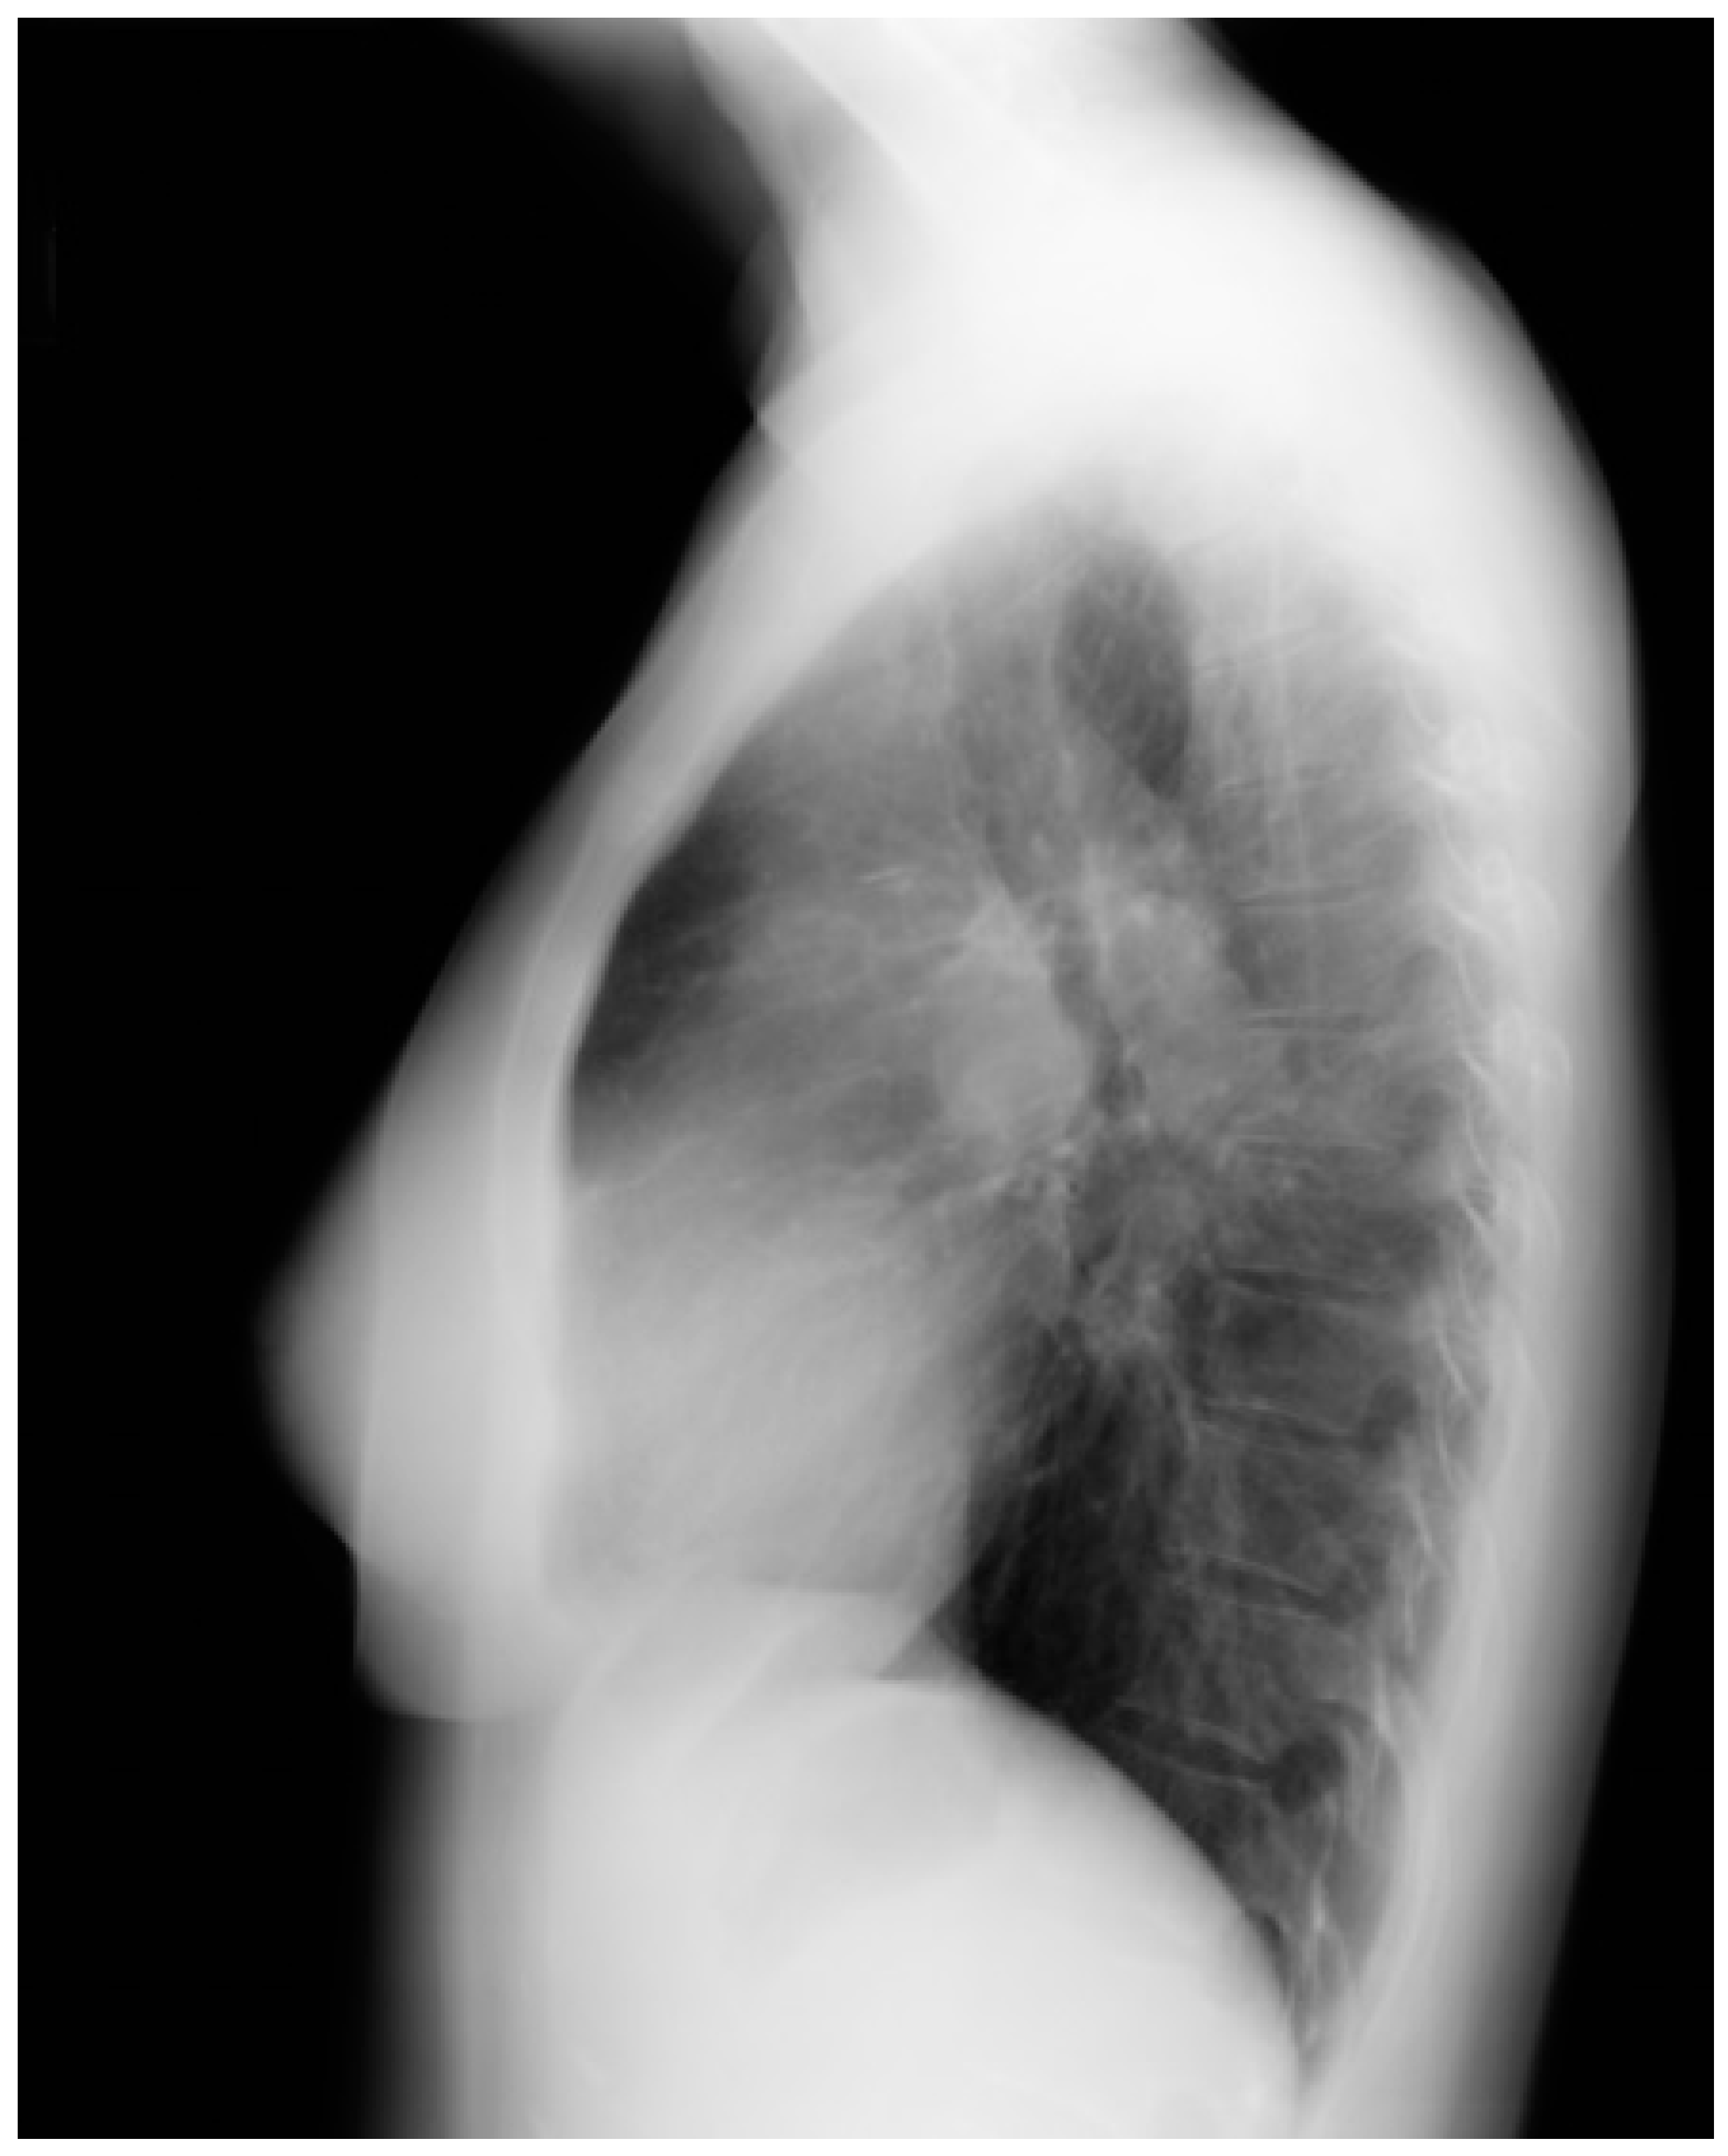

Figure 14.

Lateral chest X-ray in congenitally corrected transposition of the great arteries in adulthood: this is the lateral chest X-ray of the same 41-year-old male in Figure 13. There are sternal wires from the median sternotomy used to repair his atrial septal defect, remote from this presentation. The retrosternal airspace is opacified, suggesting right ventricular enlargement. On examination he had a holosystolic murmur of atrioventricular valve regurgitation. Doppler echocardiography demonstrated severe systemic atrioventricular valve regurgitation (the anatomic tricuspid valve), and moderate dilatation of the systemic ventricle (the anatomic right ventricle) with preserved systolic function. He underwent replacement of the systemic atrioventricular valve with a dual-tilting disc mechanical prosthesis and did well. Optimally, the transition from pediatric congenital heart disease care to adult congenital heart disease care should be a coordinated hand-off [12].